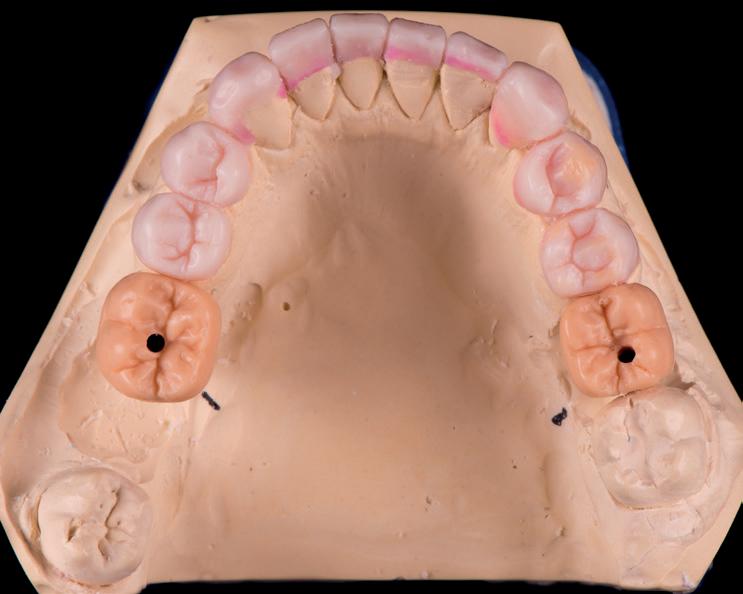

Afbeelding 3. Mock-up gebitsmodellen

Wax-up

Een wax-up is fundamenteel voor een precies behandelplan. Een individuele afdruk met een siliconen afdruk materiaal (Ho neygum; DMG), facebow registratie, wasbeet in maximale occlusie en een wasbeet in centrale relatie werden vervaardigd en verzonden naar de tandtechnicus voor het vervaardigen van een definitieve wax-up. De nieuwe hoogte, vorm en contour van de tanden werd gebaseerd op de analyse van de occlusie, dentolabiale relaties, fonetiek en de esthetische proporties van breedte en lengte. (Spear et al 2004, Magne et al 3003, Adolfi et al 2009, Gurrea et al 2014)

Nadat de wax-up goedgekeurd werd door de behandelaar en de patiënte, werd de wax-up overgezet naar de mond van de pa tiënte. Door middel van transparante siliconen mallen werd de opwas in de mond overgezet in composiet. Deze methode is erg eenvoudig toe te passen en biedt de mogelijkheid voor een tijdelijke fase voor gewenning. Aanpassingen kunnen worden gedaan aan fonetiek, articulatie en vorm van tanden om aan de wens van de patiënt te voldoen. Vanwege het veranderen van de verti cale dimensie en occlusie en articulatie